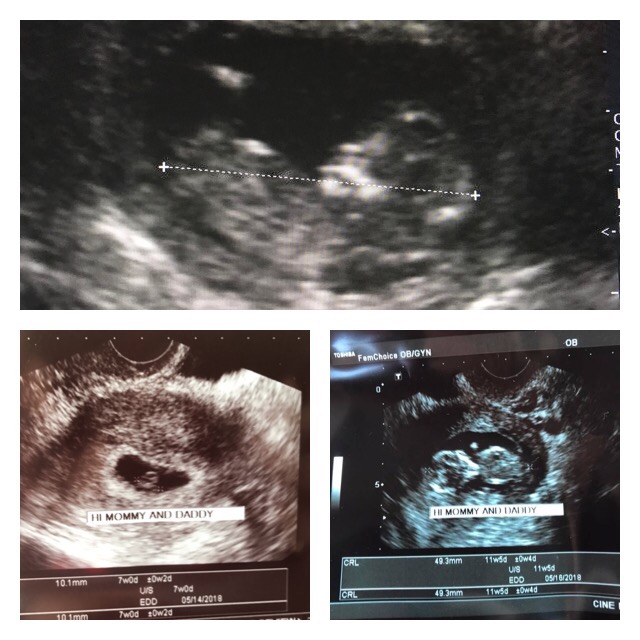

Glow is here for you on your path to pregnancy

Glow helps you navigate your fertility journey with smart tools, personalized insights, and guidance from medical experts who understand what matters most.